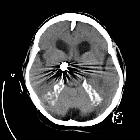

developmental and genetic origin affecting the paediatric craniofacial skeleton. Typical manifestations of nevoid basal cell carcinoma syndrome (NBCCS) in a 16-year-old boy. a Orthopantomography (OPT) shows cystic lesions of the mandible and maxilla (arrows), with unilocular and multilocular pattern and smooth or scalloped borders associated with displaced and unerupted permanent teeth. b Coronal CT scan (bone window) shows ectopic calcifications of the falx cerebri and tentorium cerebelli (arrows) and spotted meningeal calcifications (arrowheads). Brain MRI reveals a cavum veli interpositi on axial T2 (asterisk in c) and coronal contrast-enhanced T1 (asterisk in d) and also vermian dysgenesis (arrowheads in d)